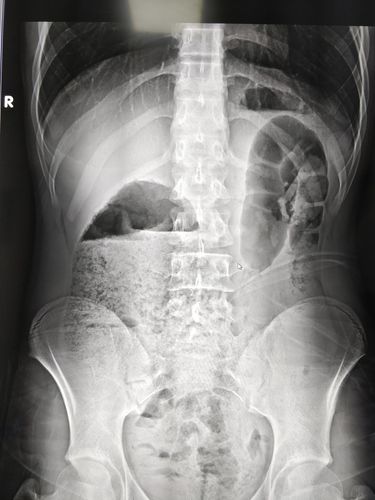

腹部立位平片

腹部立位平片,腹部平片正常

腹部平片看消化道穿孔

标准腹部立位片图片

腹部平片怎么看图解